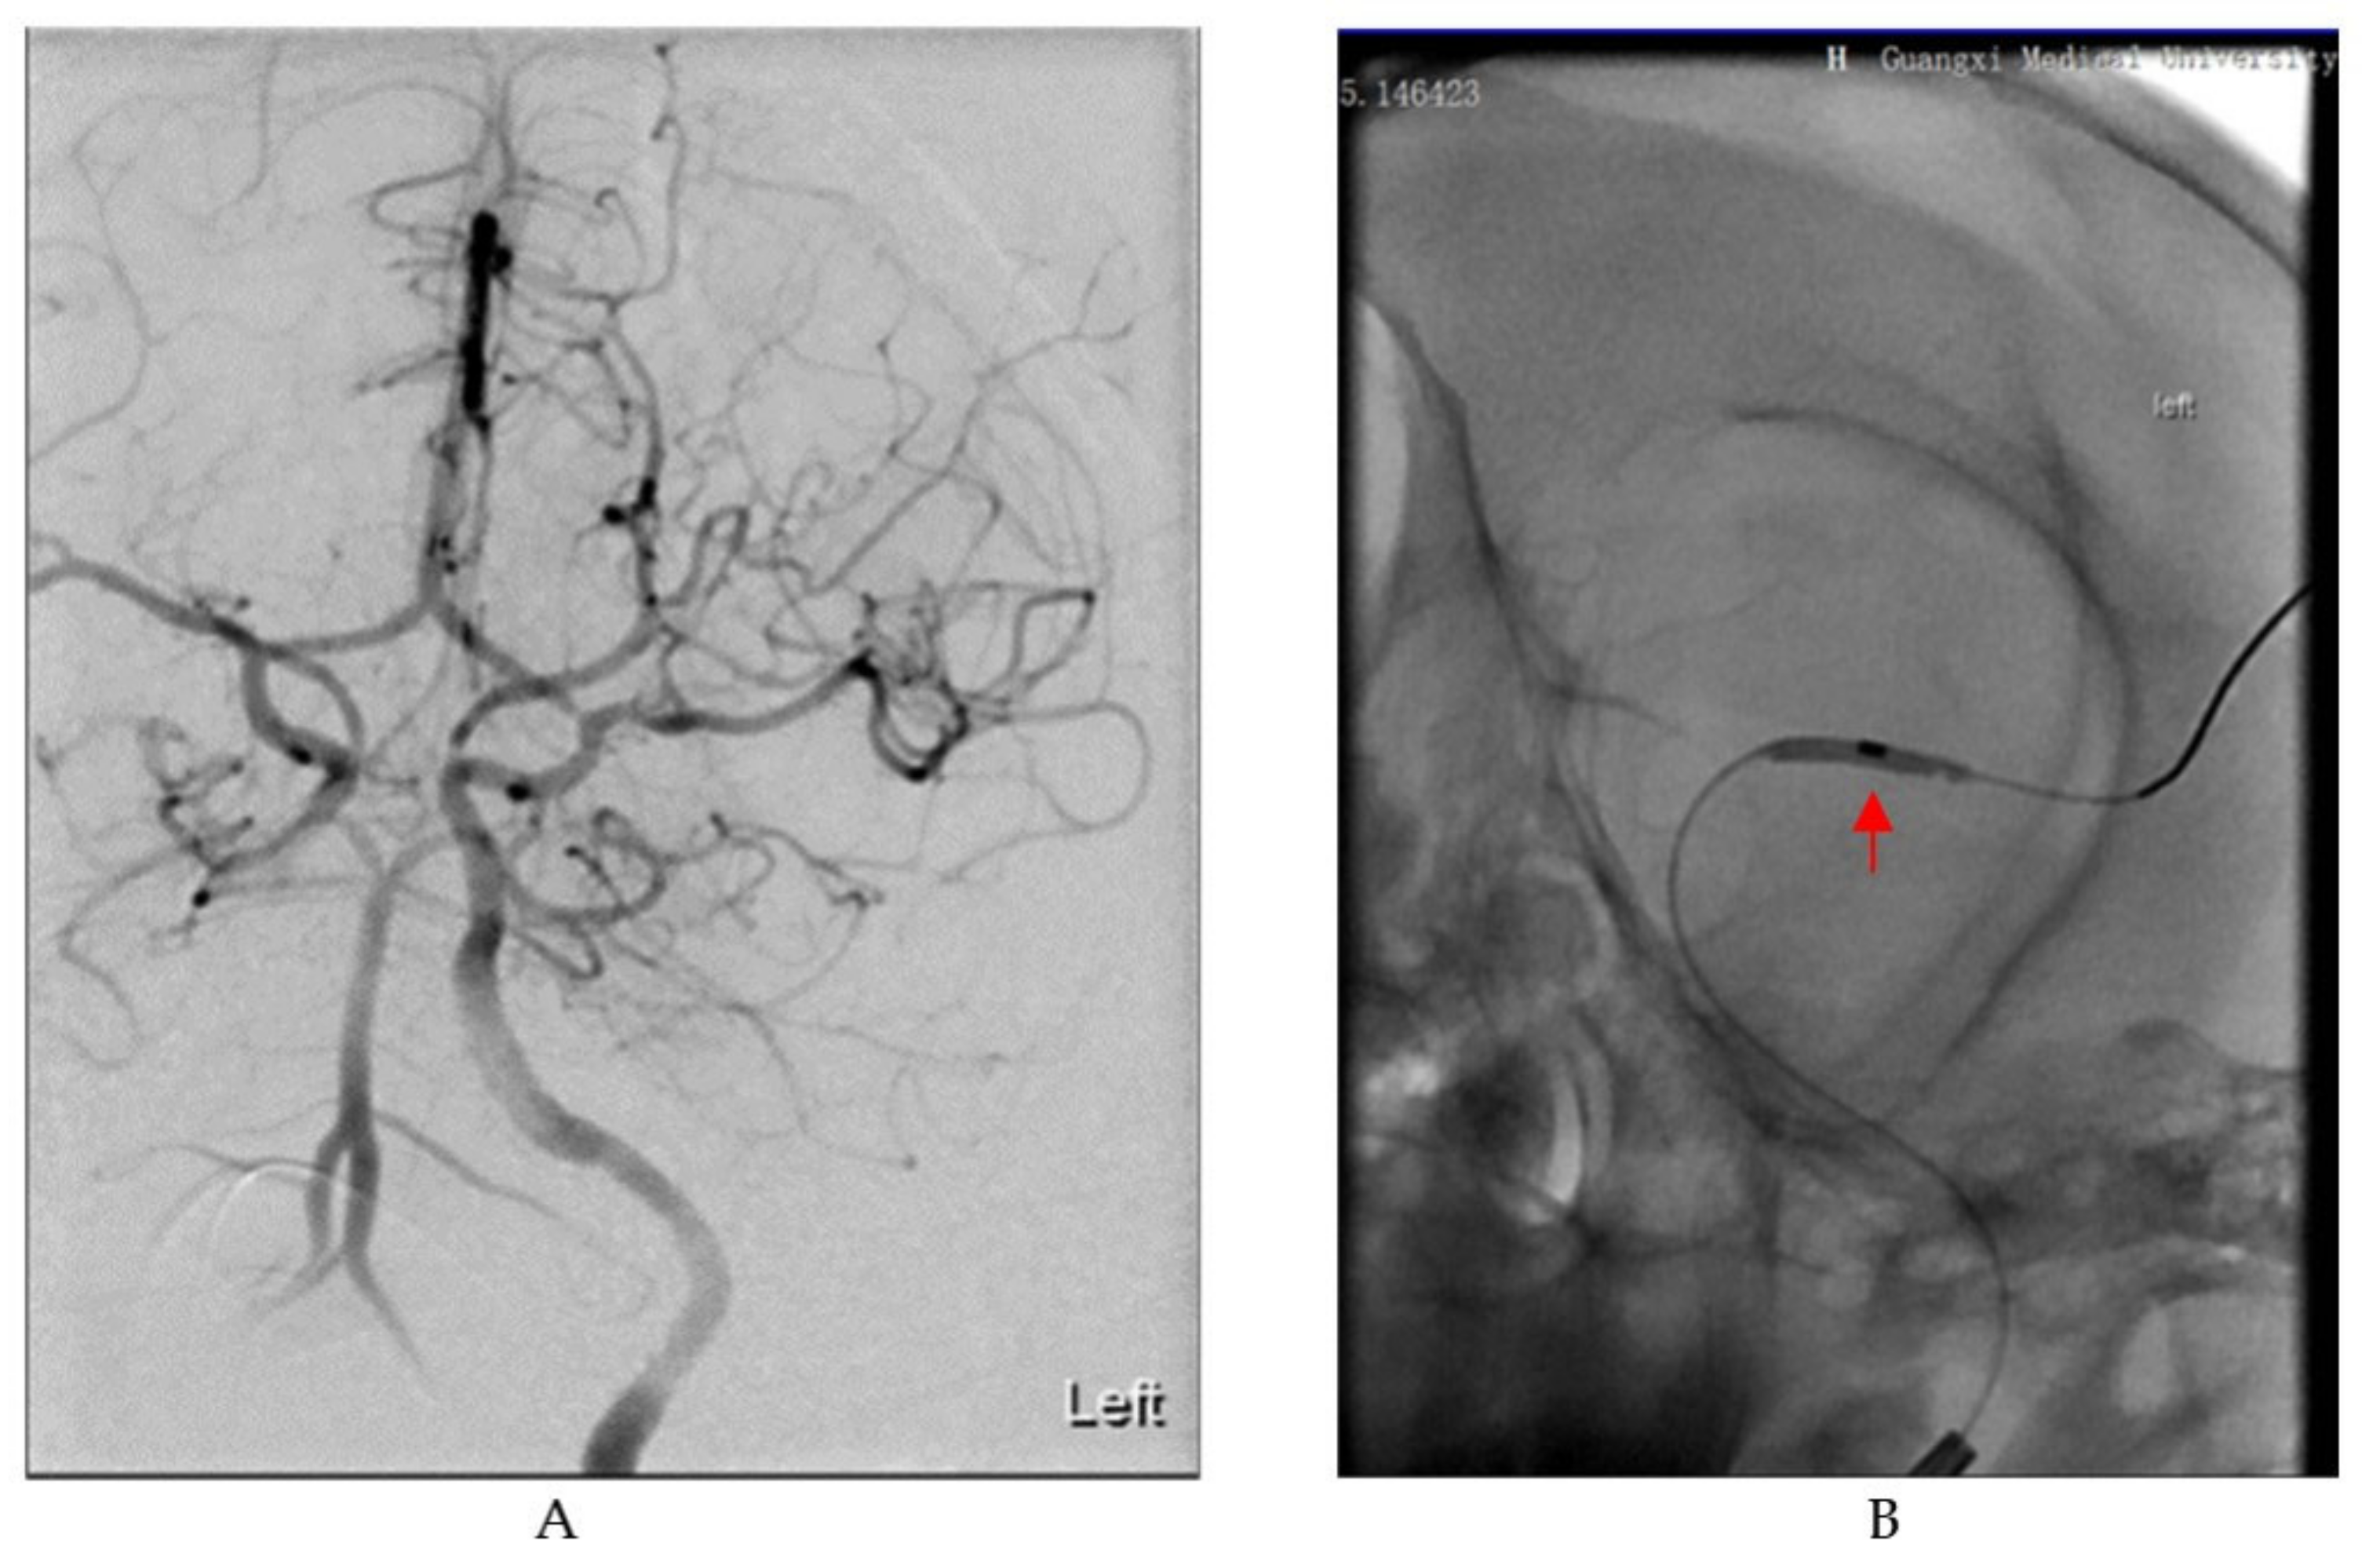

In the supine position, the animals were immobilized on the operating table. Endovascular ischemic stroke induction was performed by two skilled neurointerventional specialists. As we previously described [17], a 6 French sheath was inserted through the femoral artery. Under the guidance of a super-slippery guide wire, cerebral angiography was performed to verify catheter placement and to assess blood flow status. Imaging showed a well-developed left middle cerebral artery (MCA) with smooth blood flow (Figure 1A). Then, under the guidance of the catheter, the microcatheter (Excelsior® SL-10, Stryker, Kalamazoo, MI, USA) and microguide wire (Synchro®-14, Stryker, Kalamazoo, MI, USA) were advanced to the distal end of the M1 segment of the left middle cerebral artery. Next, the balloon (1.5 mm × 9 mm, gateway) was delivered through the microguide wire to the left MCA M1 segment and expanded to block blood flow (Figure 1B). Cerebral angiography was employed to confirm that the balloon completely occluded the MCA. The balloon was withdrawn after 75 min of occlusion. Subsequently, another angiography was performed to evaluate the recanalization of the blood vessels. The interventional devices were removed after the operation, the puncture point was compressed for 30 min, and sterile bandages were applied. Then, an MRI scan was performed on each cynomolgus macaque. Every effort was made to prevent suffering and pain in the animals. Intensive postoperative care was provided until the animals could feed themselves.

Figure 1.

Digital subtraction angiography (DSA) images in the process of establishing the cynomolgus monkey stroke model. (A) Image of cerebral vascular anatomy in cynomolgus monkeys under DSA. (B) A balloon dilates in the M1 segment of the MCA as indicated by the red arrow.